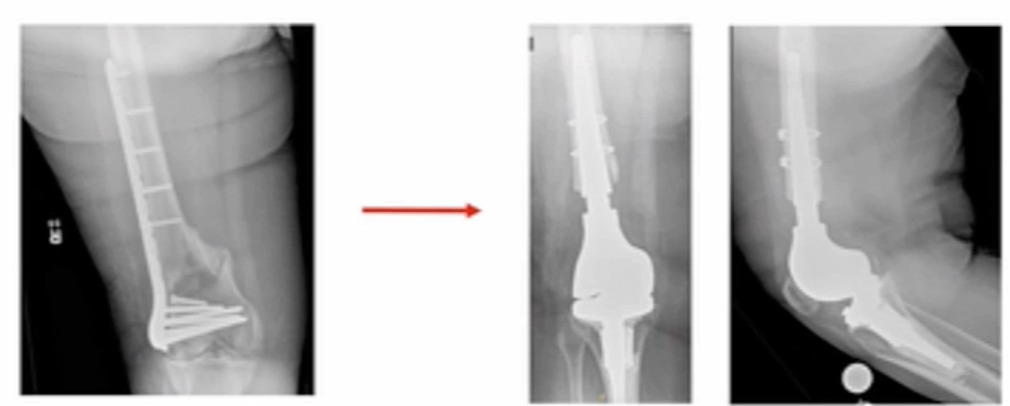

I’ve been tasked to present the Pro-Distal Femoral Replacement (DFR). It’s really not ORIF versus DFR, and which one’s better of course, that’s way too simplistic. It’s about finding the patients that are candidates for DFR and then making the decision to proceed with that. I would start with this. This is a patient I saw not too long ago; she had a distal femur fracture treated somewhere else, and she’s morbidly obese, and had a shorter steel plate implanted. (Figure 1)

This patient is at “high risk” to develop a non-union. We ultimately converted her to a distal femur replacement about nine months after her initial surgery and she asked me, “why didn’t we just do this in the first place?” It’s hard to answer.